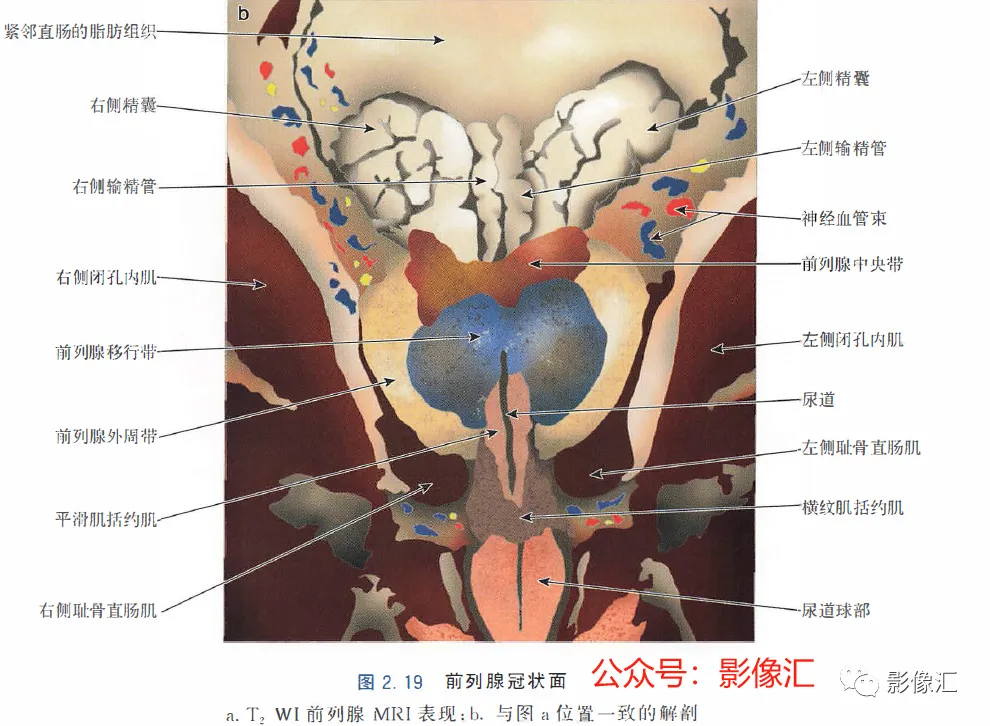

小的叶间毛细淋巴管相互吻合,形成直径逐渐增大的淋巴引流网络,直至穿过前列腺包膜并形成密集的前列腺周围淋巴引流网络。最终通过不同的途径回流到闭孔内动脉、髂外动脉、髂总动脉、腹下动脉和骶前淋巴结的淋巴链。1. 冠状面(图2.19)